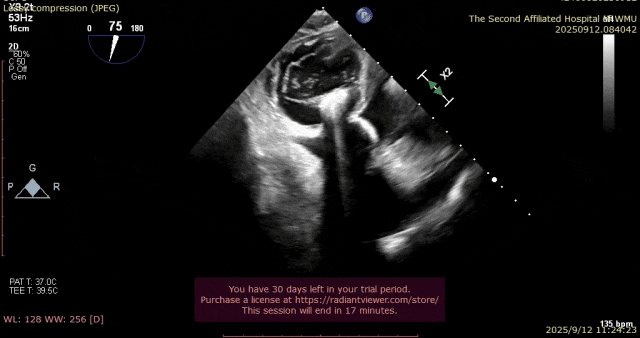

术前瓣叶

图片

术前3D